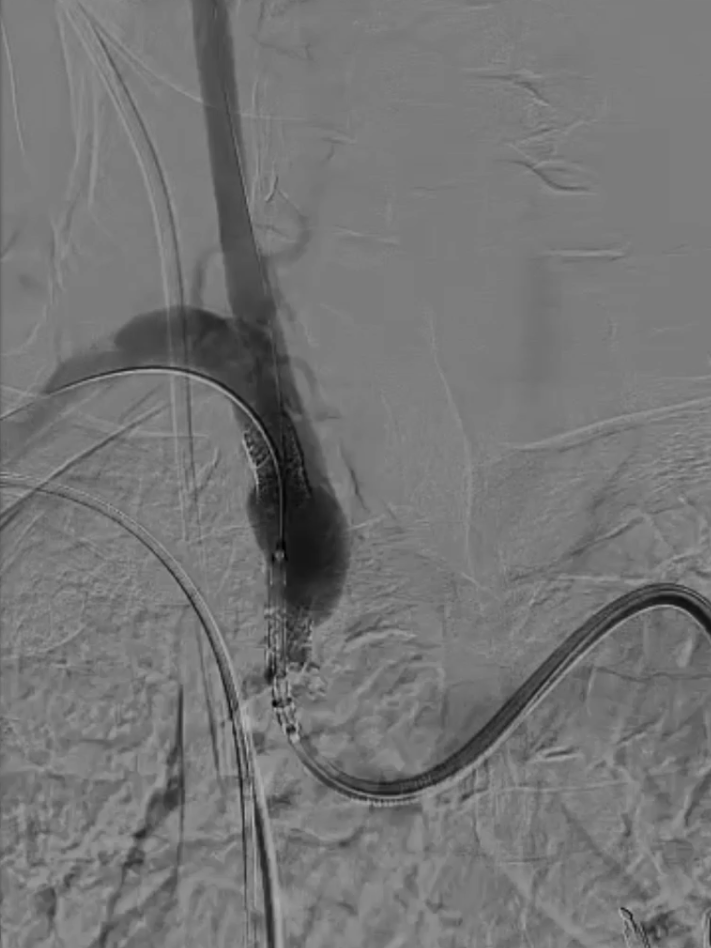

主动脉弓上造影显示无名动脉起始支架内重度狭窄,右椎动脉显影延迟,解除无名动脉支架内狭窄,恢复血流通畅,同时保障脑保护,降低并发症风险。

无名动脉起始支架内重度狭窄右椎动脉显影延迟

导丝与导管操作:超滑导丝配合多用途导管选入无名动脉,调整角度进入右锁骨下动脉;因主动脉弓扭曲严重,更换支撑导管通过病变段并造影证实

超选入无名动脉

无名动脉起始支架内

重度狭窄